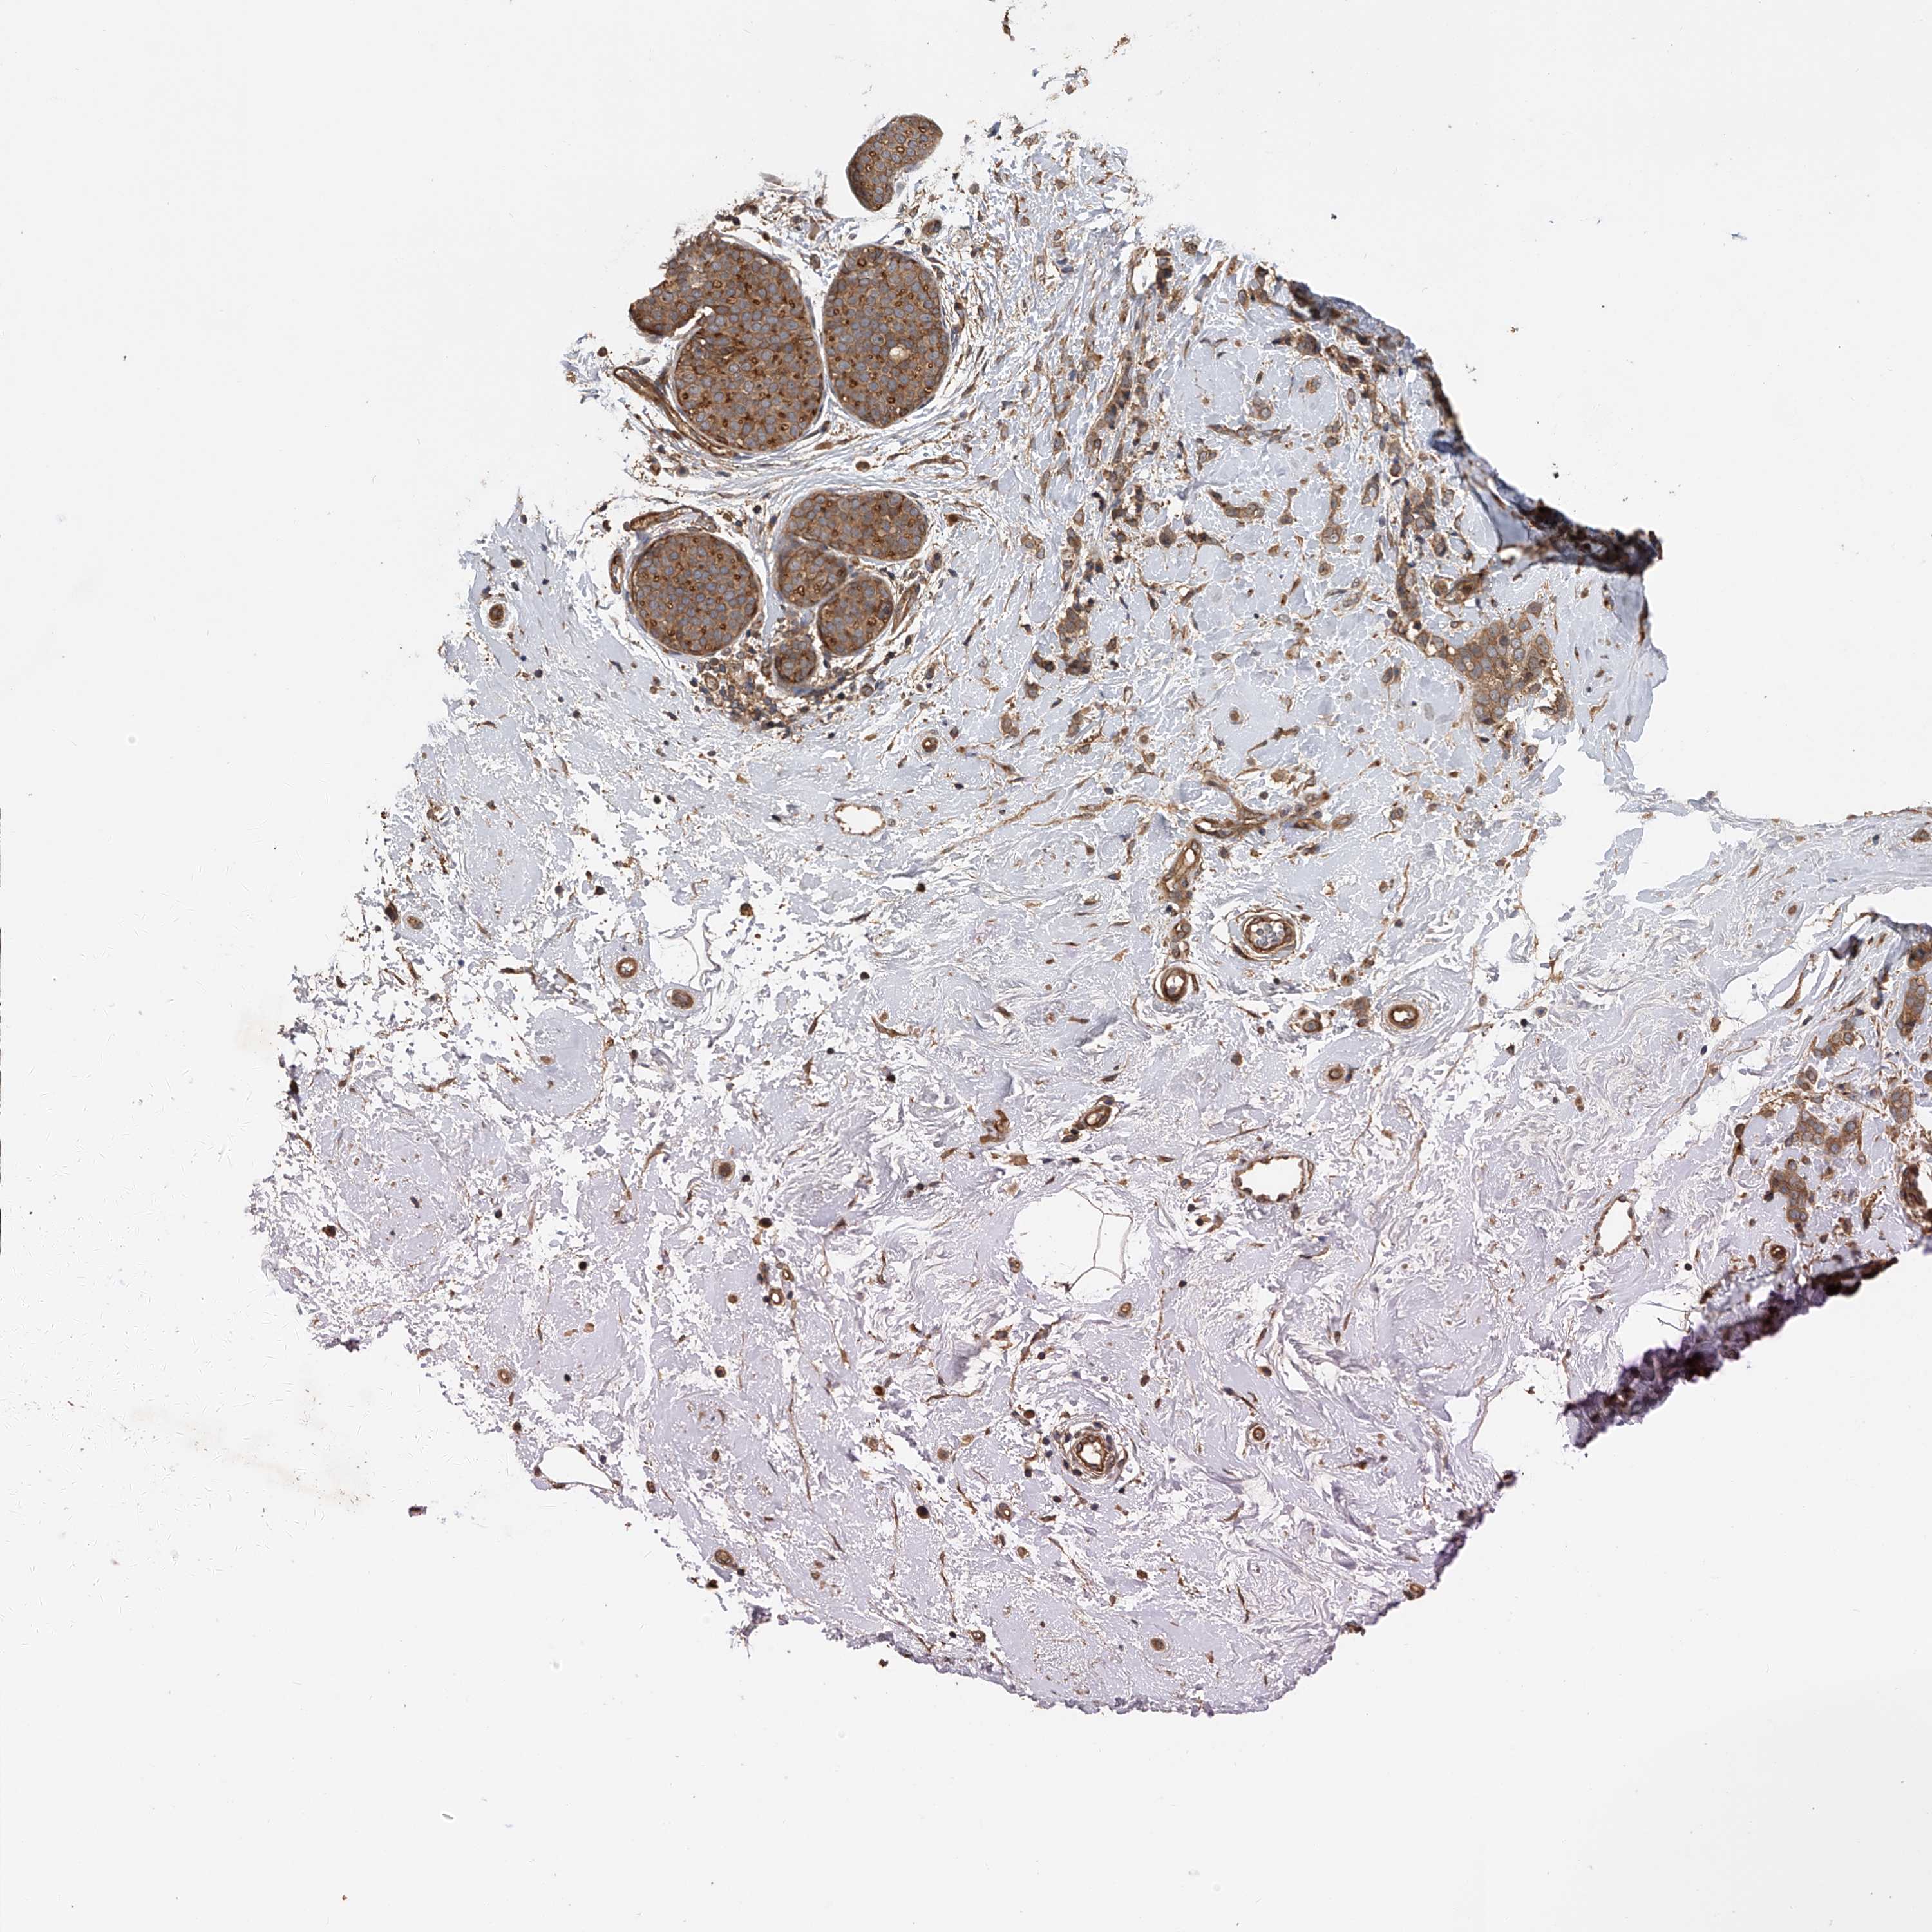

CANCER BREAST CANCER Show tissue menu

BRCA TCGA BRCA VALIDATION PROTEIN EXPRESSION